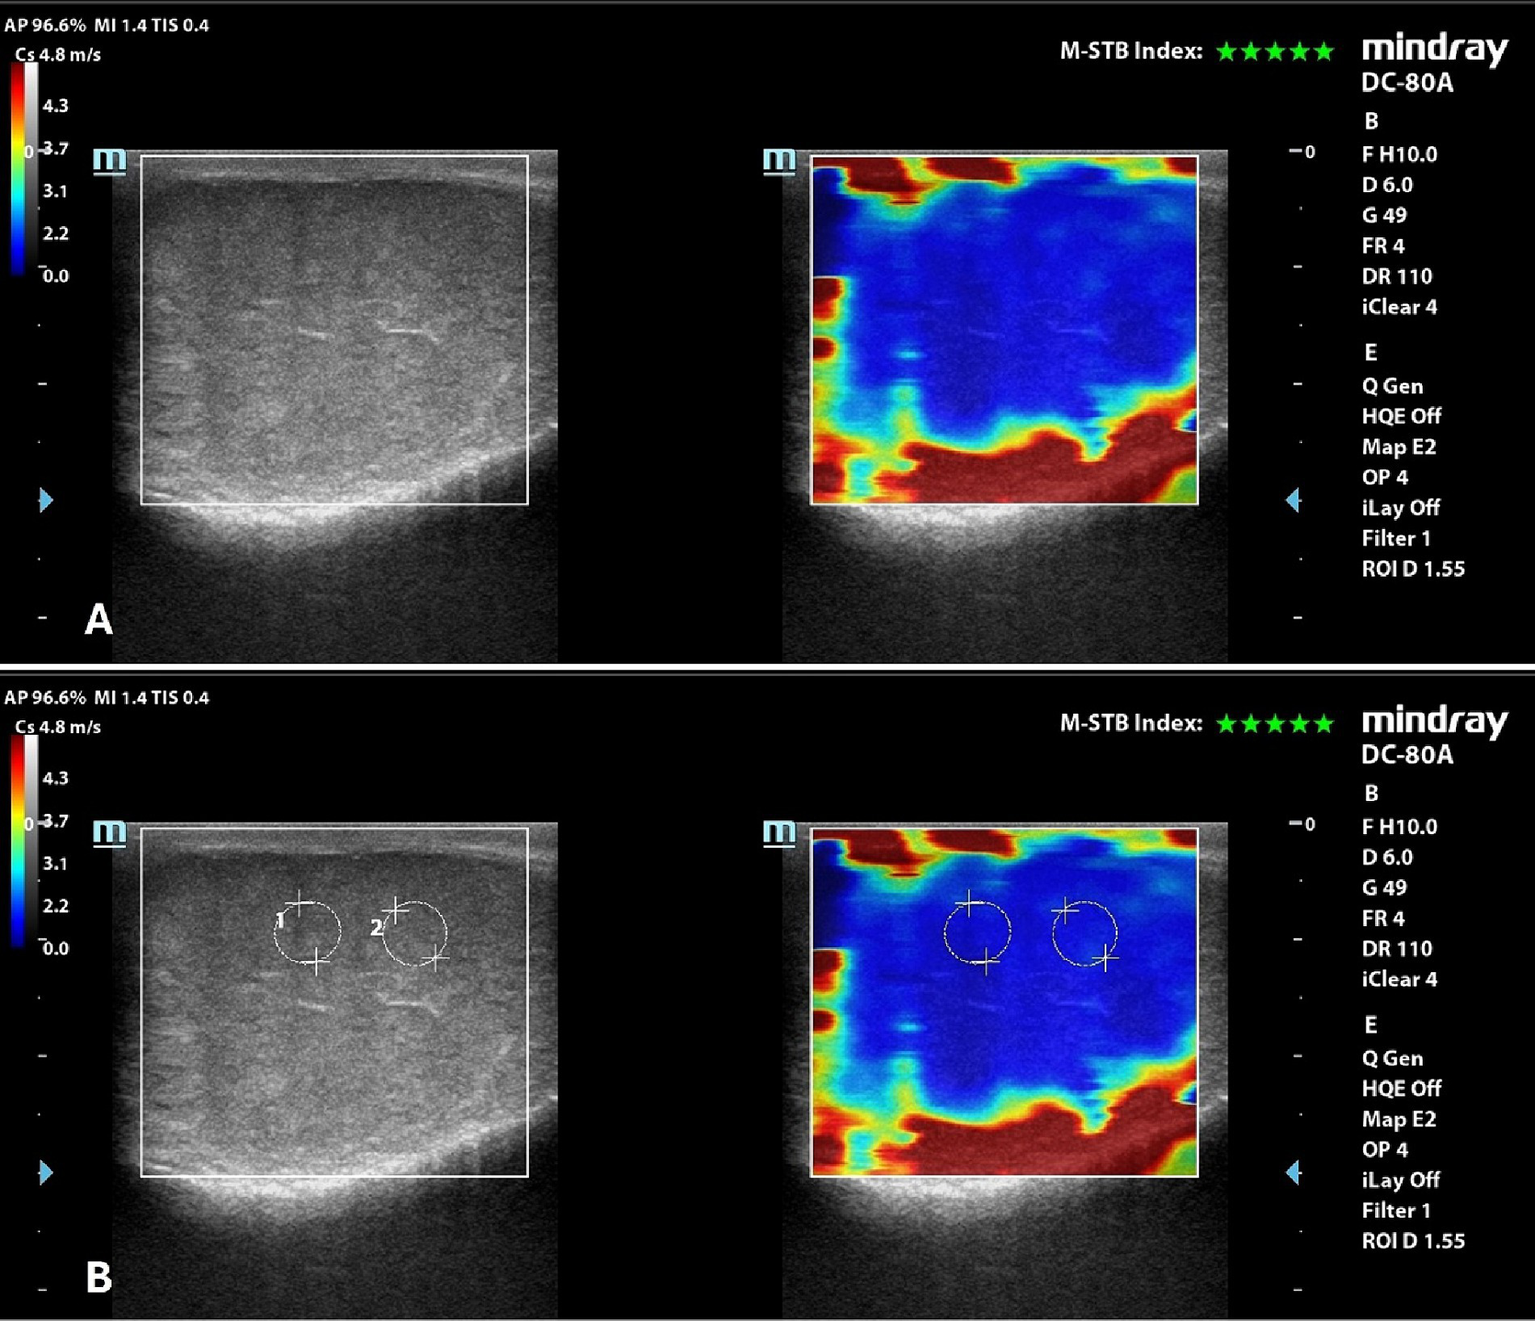

2D-SWE

Eighteen pairs of testes were evaluated by 2D-SWE and 72 SWS measurements were obtained.

Qualitative analysis showed a uniform blue pattern in the testicular parenchyma, while the surrounding structures (testicular involutes) appeared as a colored border from green to red, following the gradient of the scale, from the internal to the external part of the FOV (Figure 3). Results of quantitative analysis, Mean, with the respective 95% confidence interval (CI), standard deviation (SD), minimum and maximum values, expressed m/s, are reported in Table 5.

Figure 3

2D-SWE of a normal dog’s testicle, with a dual image showing the B-mode on the left and the elastogram on the right; (A) qualitative assessment; (B) quantitative assessment obtained by placing 2 round ROIs in the testicular parenchyma above the mediastinum line.

No significant differences were found between left and right testicles (p = 0.061), and between measurement taken above (1.64 ± 0.15 m/s) and below (1.66 ± 0.15 m/s) the mediastinum line (p = 0.486). There were no significant differences also in measurements between breeds (p = 0.249).

A significant positive correlation was found between testicular stiffness and weight of dogs. No correlation was found between 2D-SWE values and age, BCS, testicular volume, and prostatic volume of the evaluated patients (Table 6).